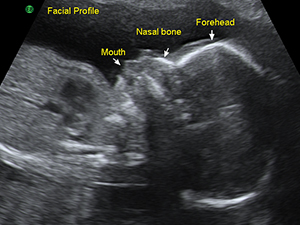

Second Trimester - Head and Face